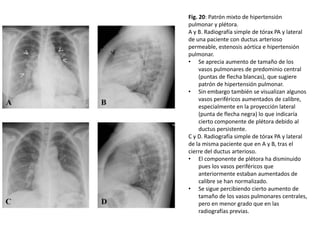

Fig. 20: Patrón mixto de hipertensión

pulmonar y plétora.

A y B. Radiografía simple de tórax PA y lateral

de una paciente con ductus arterioso

permeable, estenosis aórtica e hipertensión

pulmonar.

• Se aprecia aumento de tamaño de los

vasos pulmonares de predominio central

(puntas de flecha blancas), que sugiere

patrón de hipertensión pulmonar.

• Sin embargo también se visualizan algunos

vasos periféricos aumentados de calibre,

especialmente en la proyección lateral

(punta de flecha negra) lo que indicaría

cierto componente de plétora debido al

ductus persistente.

C y D. Radiografía simple de tórax PA y lateral

de la misma paciente que en A y B, tras el

cierre del ductus arterioso.

• El componente de plétora ha disminuido

pues los vasos periféricos que

anteriormente estaban aumentados de

calibre se han normalizado.

• Se sigue percibiendo cierto aumento de

tamaño de los vasos pulmonares centrales,

pero en menor grado que en las

radiografías previas.